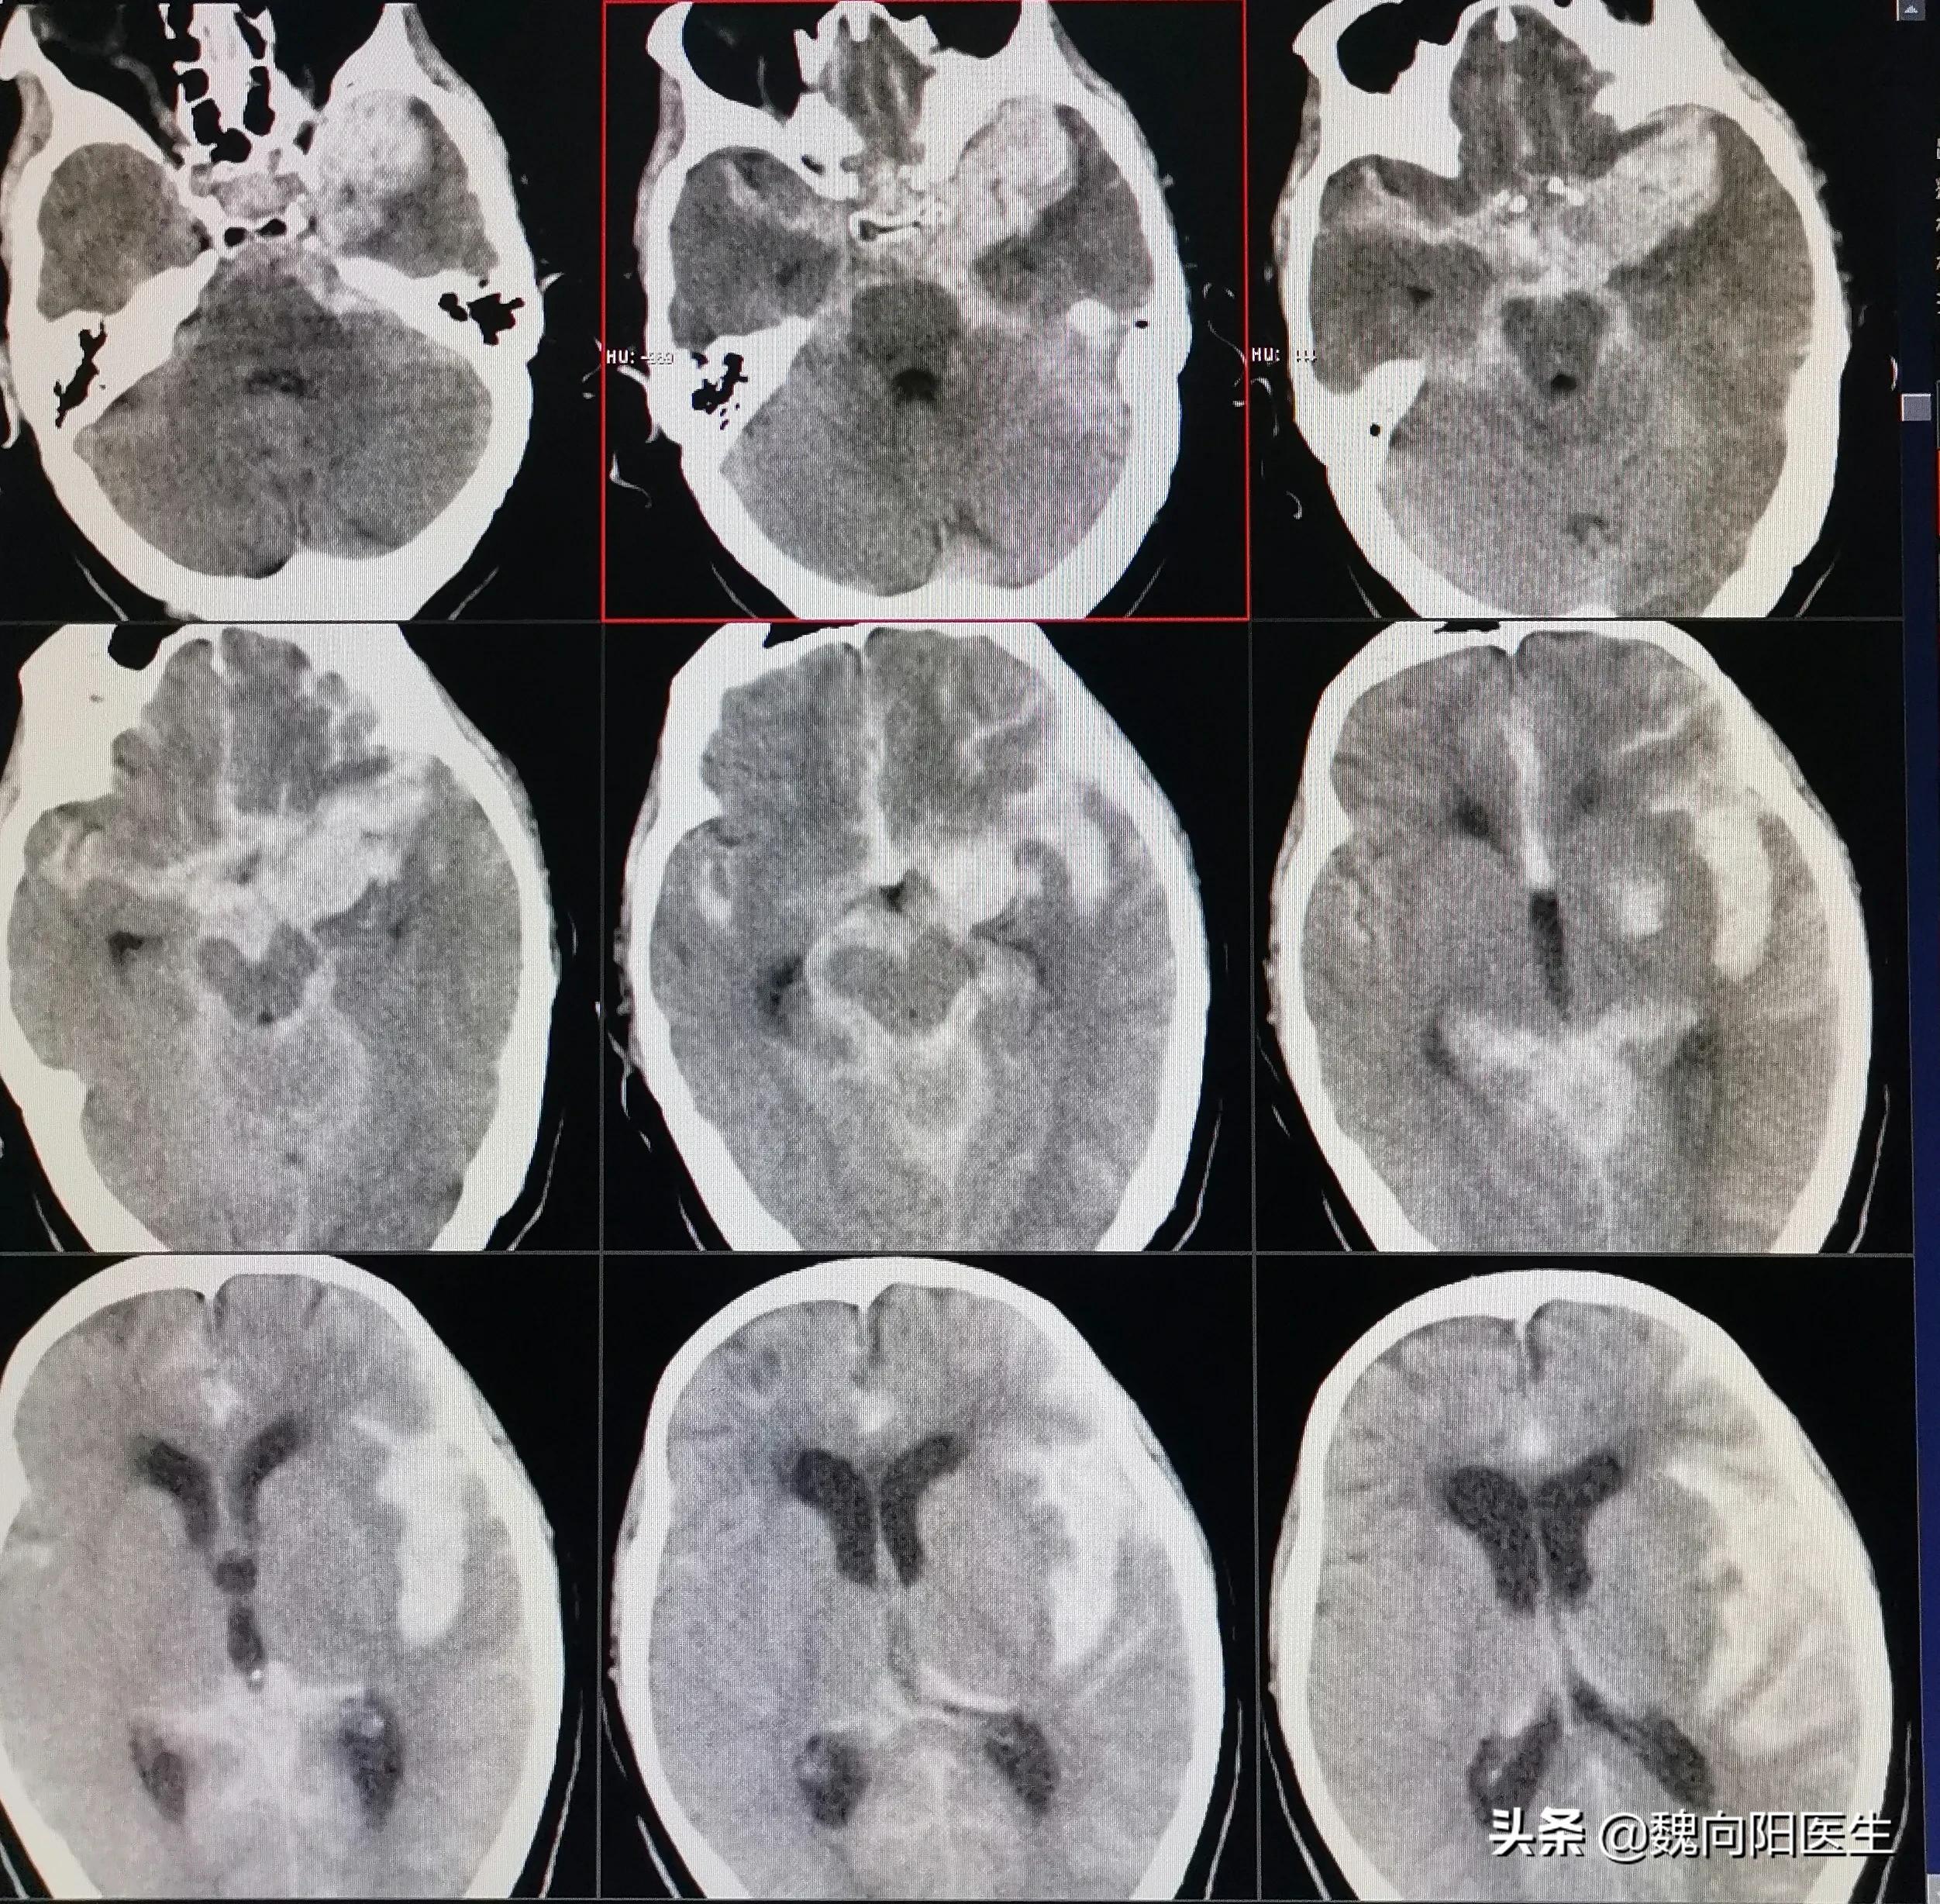

当送至我院后,再次复查头CT发现:“患者蛛网膜下腔出血较前增多,伴双侧侧脑室扩大”,且患者和昏迷状态更加严重,出现了呼吸困难情况,在急诊立即给予经口气管插管术,给予呼吸机辅助通气治疗。患者目前的意识状态逐渐加重,考虑是患者急性蛛网膜下腔出血并发急性脑积水导致,且脑积水情况进行性加重,立即给予侧脑室穿刺引流,改善脑室积水。诊断周某是自发性蛛网膜下腔出血,不排除患者出血原因是颅内动脉瘤破裂导致,因此建议立即行脑血管造影检查,明确发病原因,并给予有针对性的治疗。经患者家属同意后,立即联系介入导管室,给予全麻下脑血管造影发现:“小脑后下动脉动脉瘤”,经过分析考虑该动脉瘤为责任病灶,如果不处理该动脉瘤,则第二次出血风险高,且一旦再次出血后症状会更加严重,甚至危及生命。

经过近半月的脑室持续脑脊液引流,颅内蛛网膜下腔及脑室内血性脑脊液基本消失,急性脑积水症状得到了根本控制,患者意识症状也明显好转,也拔除气管插管,可以自主正常呼吸。等待到1月左右时,患者可以与人正常交流,并可下地缓慢行走。且患者未再发生蛛网膜下腔出血。